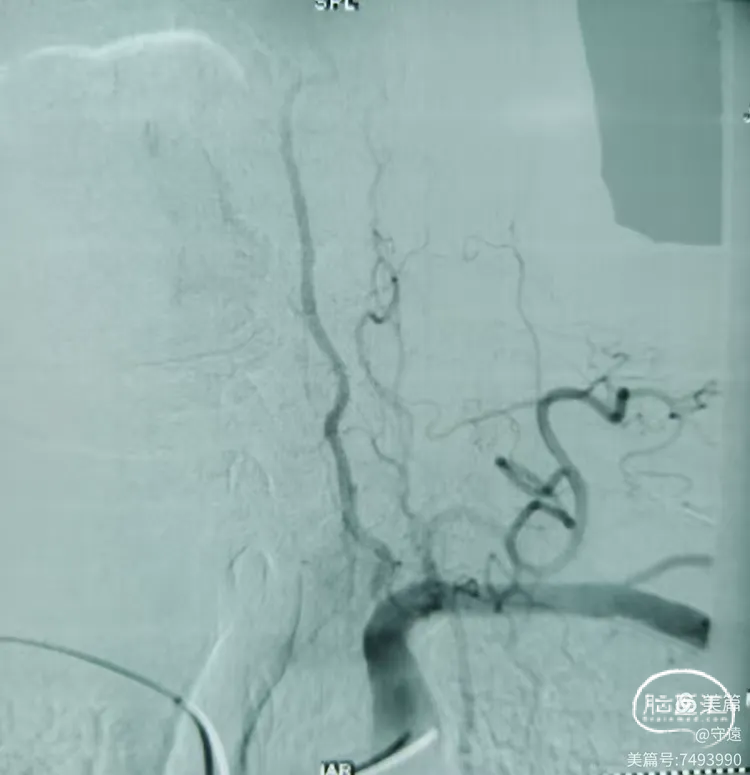

经桡动脉造影:左侧椎动脉起始终部中度狭窄。向颅内供血缓慢,v4段闭塞。

右侧椎动脉为优势椎,血流迟滞,V2以远未显影,考虑V4 闭塞。